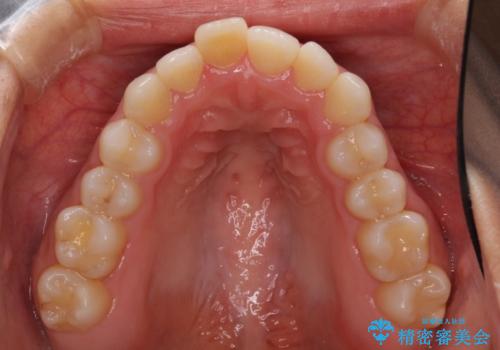

- 上下の前歯のデコボコと奥歯の反対咬合を気にして来院された患者様です。

インビザラインを用い、上下顎ともにIPR(歯と歯の間を削る)により叢生を改善することとしました。

奥歯の反対咬合は、骨格に由来するものであるため、改善できるところまで改善していくこととしました。

治療を長期化させたくないとのご要望があったので、左下の90度捻転した歯は、捻転した状態のゴールとしました。

反対咬合を改善したことで、歯ぎしりしたときの引っかかる感じがなくなり、奥歯への負担を大きく軽減することができました。